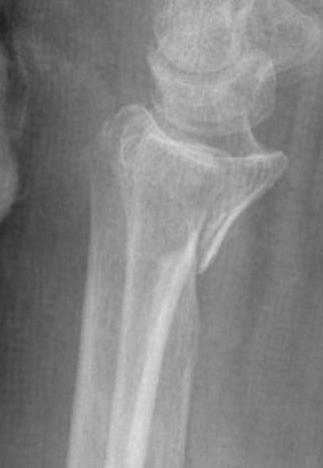

Radial styloid fractures / Chauffeur's Fracture

Associations

Perilunate fracture / dislocations

Radiocarpal dislocation

Scaphoid fractures

Options

K wires / screw fixation / radial styloid plate / volar locking plate

Approach

- volar approach

- dorsal-radial approach

Dorso-radial approach / direct approach to radial styloid

AO foundation dorso-radial approach

Between 1st and 2nd extensor compartments

- protect sensory branches radial nerve

- release brachioradialis tendon

- release 1st compartment and mobilize 2nd